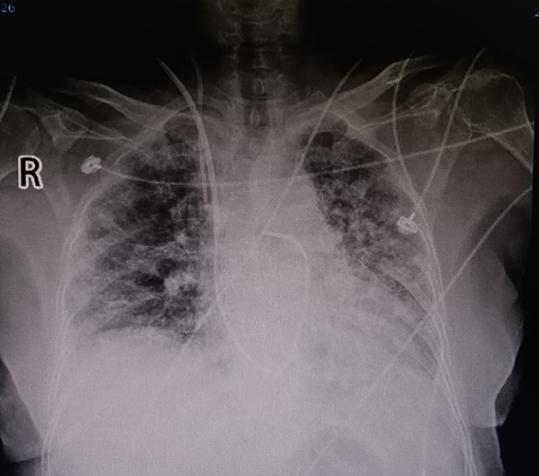

12月24日,呼吸与危重症医学科王苒副主任医师、吴冬主治医师、孙娟主治医师共同完成了安徽省呼吸内科学界首例右心漂浮导管检查+血流动力学监测,将一名患者确诊为肺动脉高压,并明确了具体类型,为下一步治疗提供了确切的方向。

肺动脉高压是由多种已知或未知原因引起的肺动脉压力异常升高的一类临床综合征,临床表现缺乏特异性,误诊、漏诊率较高,如果不及时诊断和治疗,肺血管阻力和肺动脉压力持续升高,会导致心力衰竭甚至猝死,致残率和致死率高。在靶向药物上市之前,与晚期癌症生存率几乎相当,因此肺动脉高压被称为肺血管系统的“癌症”。

右心漂浮导管检查是诊断肺动脉高压的“金标准”,右心漂浮导管检查时,配合使用血流动力学监测设备,不仅可以测定肺动脉压力,还可以评估各项血流动力学指标,如上腔静脉压、右心房压力、右心室压力、肺小动脉楔压、肺血管阻力、心排量,心指数、全肺阻力、体循环阻力等,在确诊肺动脉高压的同时,还可以明确肺动脉高压的具体类型及危险分层,从而为患者的治疗提供依据。